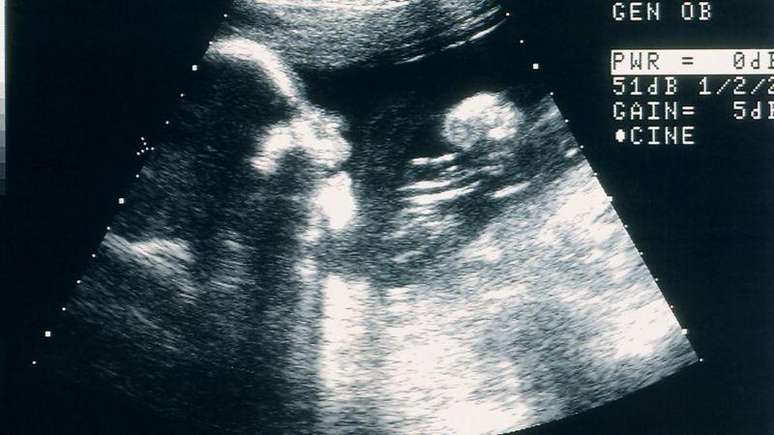

Imagem de uma ultrassonografia

Foto: Getty Images / BBC News Brasil

Avaliar o impacto psicológico de uma perda gestacional no primeiro trimestre é algo complexo.